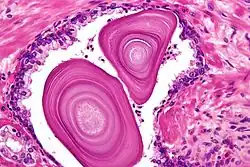

Histology of a multilayered corpus amylaceous of the prostate.

Histology of a multilayered corpus amylaceous of the prostate.